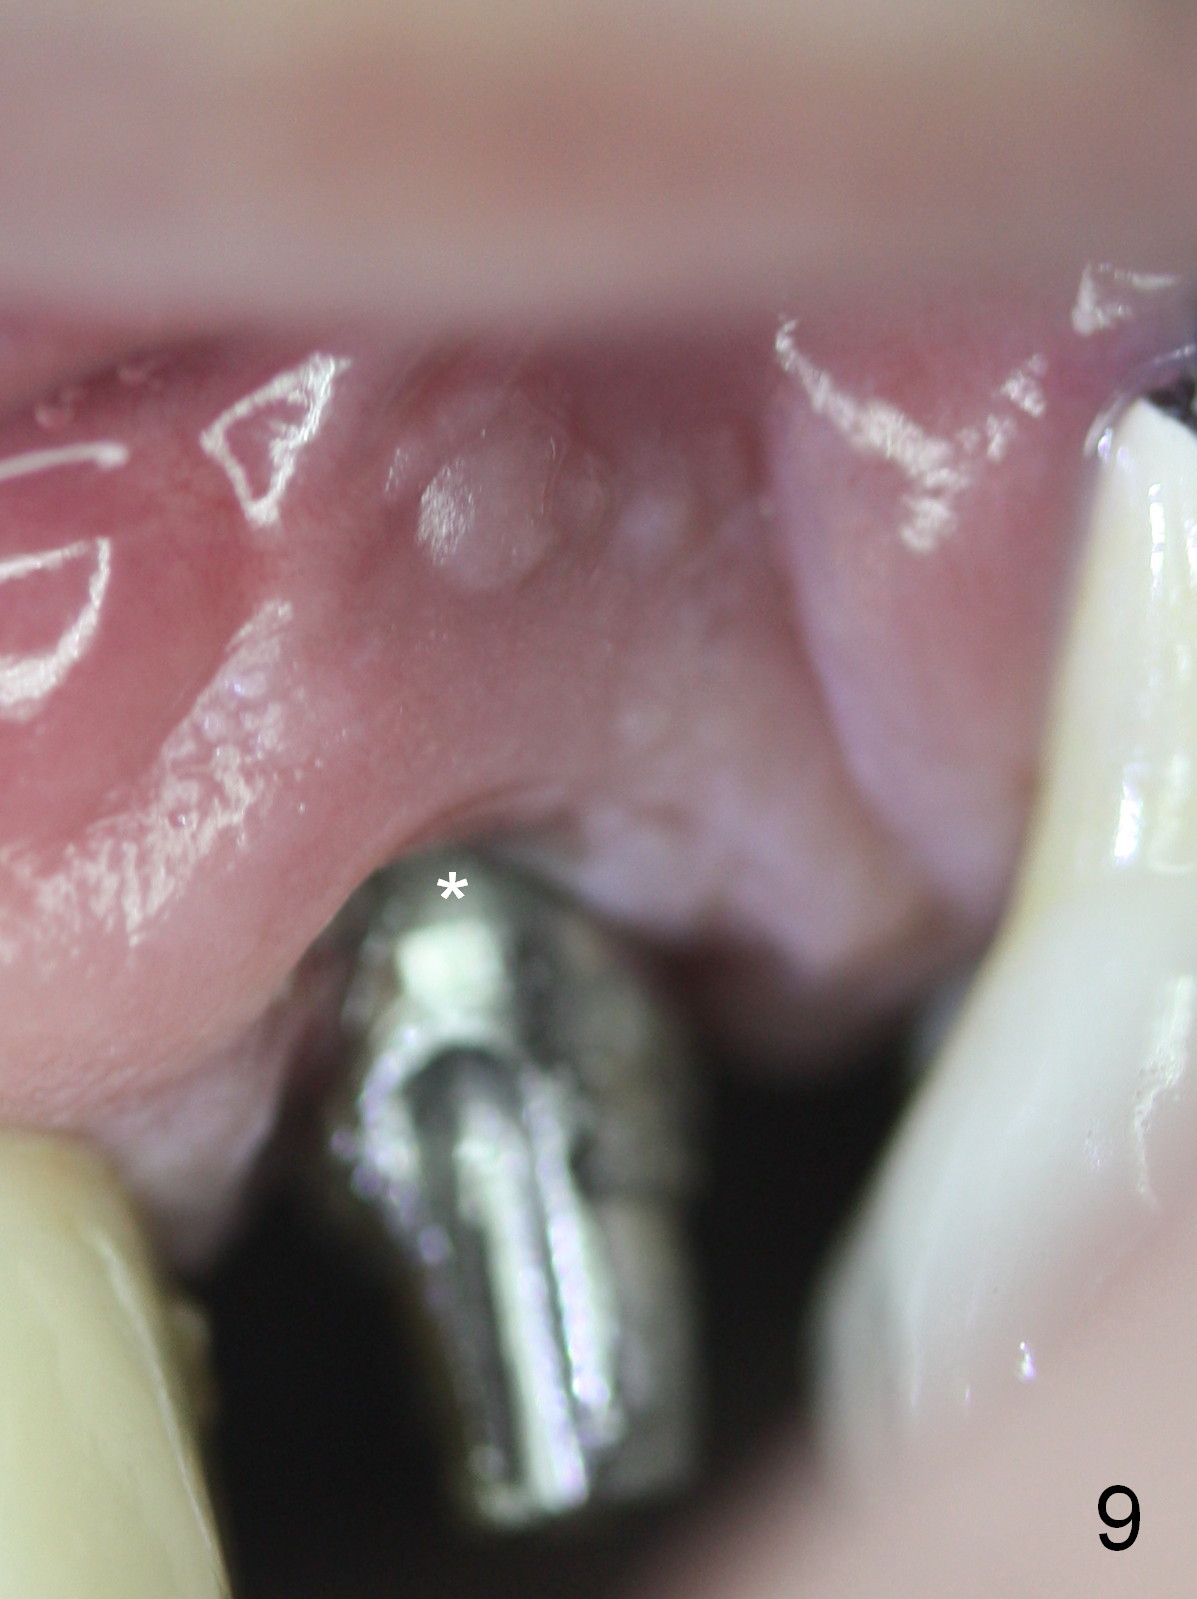

The patient returns 7 days postop, reporting that the provisional has been dislodged several times. The gingiva adapts to the provisional with occlusal clearance (Fig 8 *). The rough surface of the implant is exposed (Fig.9,10 *). It appears that some of bone graft has been lost. The provisional should be trimmed so that the gingiva may be able to grow over the rough surface.